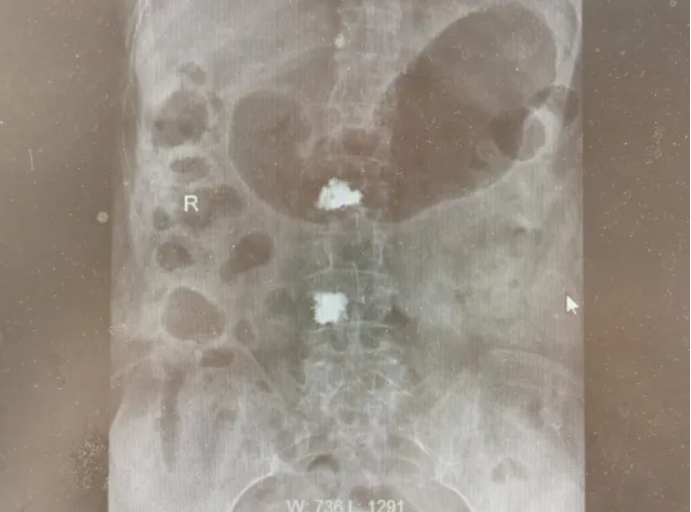

最近,我院脊柱外科先后为两位九旬老人成功实施了微创手术。93岁的张爷爷(化姓)不慎摔倒后,被诊断为胸椎T12椎体压缩性骨折;几乎同期,92岁的刘奶奶(化姓)也因腰部剧痛入院,确诊为腰椎L4椎体骨折。张爷爷有高血压、心律失常、骨质疏松等常见的基础疾病,刘奶奶则有全身症状,出现了低热、盗汗、贫血等情况。面对超高龄与基础病并存的情况,保守卧床休养存在较高的并发症风险。高龄,恰恰是更需要积极、稳妥干预的理由。

脊柱外科团队在全面、细致的术前评估后,为两位老人制定了同一种成熟可靠的微创治疗方案——经皮椎体成形术(俗称“骨水泥”手术)。

与大众想象中“开刀”的手术不同,这项技术更像是一次精准的“内部加固”。手术在局部麻醉下进行,患者全程保持清醒。医生仅在背部皮肤做一个针尖大小的微小穿刺点,在手术导航机器人的实时引导下,将一种名为“骨水泥”的生物材料精准注入骨折塌陷的椎体内。 整个过程创伤小,出血少,对心肺功能影响小,因此特别适合高龄、体质偏弱的患者。这并非一项挑战极限的技术,而是基于患者实际身体状况所做出的周全选择。

手术与后续管理方案非常顺利。术后不久,两位老人的疼痛便得到了显著缓解。张爷爷终于能安稳翻身,刘奶奶则在医护人员帮助下,很快佩戴护具坐起,并尝试下床站立、缓步行走。值得一提的是,刘奶奶是“第二次”选择这项技术。6年前,她就曾因腰椎L2骨折在我院接受过相同的“骨水泥”微创手术,术后多年行动自如。此次再发骨折,她和家人毫不犹豫地再次选择了我们。这份沉甸甸的信任,是对脊柱外科团队从手术技术到全程管理能力的认可。刘奶奶笑着感慨:“还是这里让人安心,上一次手术让我好了这么多年,这次又让我少受了罪。”